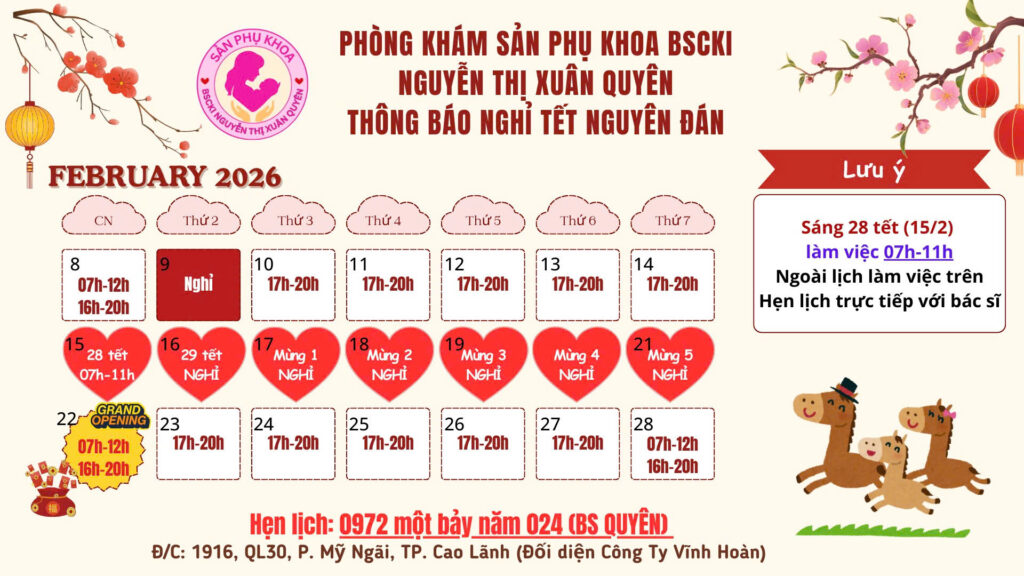

Bảng Giá tham khảo

Gói dịch vụ

Gói kiểm tra tiền hôn nhân nâng cao

gói kiểm tra tiền hôn nhân cơ bản

gói kiểm tra phụ khoa cơ bản

gói đánh giá chức năng sinh sản

Bảng Giá tham khảo